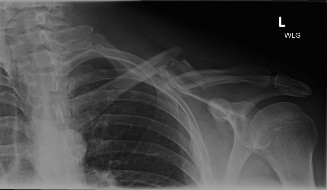

Middle-third clavicle fractures represent a substantial portion of orthopedic trauma, accounting for 2-10% of all fractures and 45-80% of all clavicle fractures. The clavicle is the most commonly fractured bone in the adult population. Its subcutaneous location and biomechanical role as a strut connecting the axial skeleton to the upper extremity render it vulnerable to injury. These fractures exhibit a bimodal distribution, with a high incidence in young, active males due to high-energy trauma and in elderly females often associated with osteoporosis and low-energy falls.

The mechanism of injury is typically a direct blow to the superior aspect of the shoulder, or an indirect force transmitted through the arm during a fall onto an outstretched hand. Associated injuries, though uncommon for isolated midshaft fractures, can include scapular fractures, rib fractures, pneumothorax, brachial plexus injury, or subclavian vessel compromise. This is particularly true in high-energy trauma or highly displaced fractures. A thorough neurovascular examination is paramount in the initial assessment.

Accurate classification is essential for guiding treatment and standardizing research. The Allman classification divides the clavicle into thirds, with Group I representing middle-third fractures. The Robinson classification provides a more granular prognostic framework for midshaft fractures (Type 2). Within Robinson Type 2, injuries are subdivided based on displacement and comminution. Type 2A represents non-displaced fractures, while Type 2B represents displaced fractures. Type 2B is further subdivided into 2B1 (simple or single butterfly fragment) and 2B2 (comminuted or segmental). This distinction is critical, as Robinson Type 2B2 fractures carry a significantly higher risk of nonunion when managed non-operatively.

Absolute indications for surgery include open fractures, vascular compromise requiring repair, and progressive neurologic deficit. Relative indications, which form the bulk of surgical volume, center on fracture displacement and shortening. Extensive literature demonstrates that shortening greater than 2 centimeters and complete fracture displacement are independent predictors of nonunion and poor functional outcomes, including decreased shoulder endurance and altered scapular kinematics.